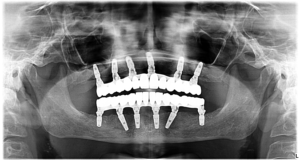

Am reușit să realizăm încă o transformare miraculoasă pentru pacienta noastră, care își dorea de mult un zâmbet perfect din punct de vedere estetic, dar mai ales funcțional.  Masticația este un proces important, ce are impact asupra sănătății generale. Atunci când aceasta nu poate fi realizată în mod corect, totul corpul are de suferit. Cum i-am redat sănătatea pacientei noastre?

• Am inserat 6 implanturi la maxilar și 6 la mandibulă

• Am folosit tehnica Sinus Lift – pentru a adăuga înălțime osului din jurul sinusurilor maxilare. Acest lucru a fost necesar deoarece am observat că în acea zonă era prezentă o insuficiență osoasă.